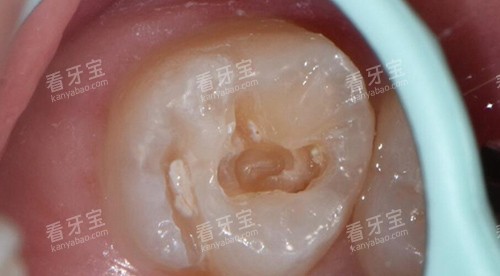

补牙:进口树脂补牙298元起,树脂补牙约300元起/颗,补牙202元起。